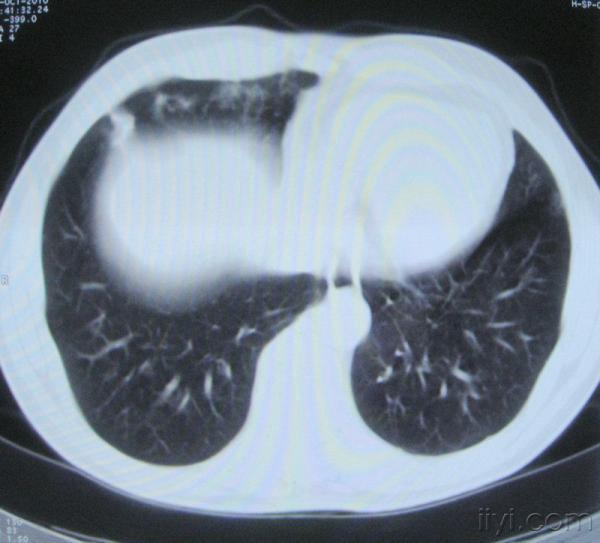

男。60岁,胸片示支气管炎治疗后复查CT。

你指那个肯定是淋巴结,中央系坏死,这很常见,特别在双侧腹股沟会经常看到。这个双侧腋窝及纵隔见多发小淋巴结征。

根据位置考虑应该是淋巴结,密度不均,是因为肿大的淋巴结中心液化坏死